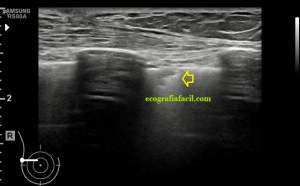

El paciente viene por un bulto en la parte derecha de la espalda, en la región paradorsal alta. Con una sonda de alta frecuencia accedo a la región, que era palpable. Lo primero que observo es que la transmisión del paciente no es buena, esto que a veces pasa que encuentras pacientes, que no sé explicar el motivo, no transmiten bien.

Me da para observar que en la zona de palpación encuentro, profundo en la imagen, un formación hiperecogénica, que está dentro de un músculo. Antes de detallar los hallazgos de la imagen lo que quise fue reconocer bien la anatomía. La piel y el tejido celular subcutánea era muy fácil, también saber que esta anatomía superficial estaba intacta y que la lesión estaba intramuscular, pero me encontraba dos planos musculares, uno superficial, el otro profundo, el profundo con la lesión.

El protocolo es el típico, cortes en eje corto y largo, con doppler, para comprobar vascularización, como línea roja del lipoma. Imágenes 3,4 y 6.

Después con la radióloga, hicimos una imágenes con «panoramic view» que te dan un detalle de las anatomía con respecto del lado contralateral, sano. Imagen 1.

La lesión era ovalada, hiperecogénica, ocupaba gran parte del músculo, pero respetaba parte de este, que era hipoecogénico (imagen 5), recuerda que así es por definición y que ésta ecogenicidad del músculo es referencia para el resto de ecogenicidades del aparato locomotor. Como te he contado, no había doppler color ni en modo angio.